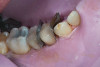

(2.) Preoperative retracted view.

Figure 2

A 34-year-old male patient with no medical issues presented to the office with the chief complaint of a failing crown on tooth No. 12. The patient was also unhappy with his bite and the appearance of his teeth (Figure 1 and Figure 2).

A comprehensive examination was carried out, and preoperative photographs were taken (Figure 1 through Figure 4). The patient presented with fair oral hygiene and slight, generalized tissue inflammation. Caries and defective restorations were detected on teeth Nos. 4, 5, 13, and 14. The crown on tooth No. 12 was showing signs of leakage, and although the endodontic access cavity had been temporarily restored with composite, this endodontic re-treatment was acceptable and the tooth was otherwise symptom-free. Erosion was present on most of the posterior teeth and the cuspids, and abrasion was noted on teeth Nos. 4, 5, 10, 11, 20, 21, 22, 28, and 29. An examination of the patient's muscles, joints, and bite revealed no joint sounds, a normal range of motion, and negative joint load and immobilization tests.

The dentofacial examination revealed a low smile line with no incisor display when the lips were in repose. The anterior teeth were chipped and worn, and their overall color was darkened. The buccal corridors were deficient, and the failing crown on tooth No. 12 was visible in a full smile.